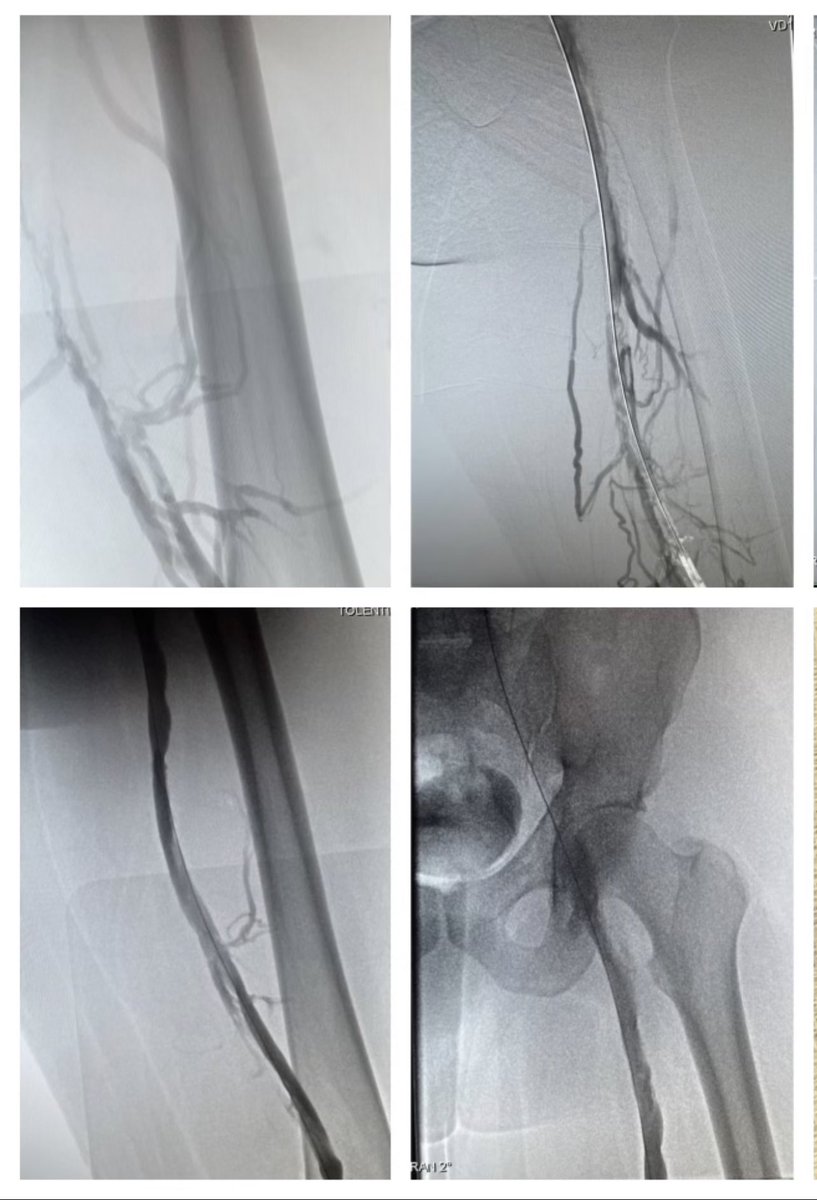

Proud to make private practice and technical education possible. Highlighting venous disease is an honor. #justacommunityhospital Line Monkey MD ASM Saud Ahmed Elie Balesh, MD Adeel Shahid, MD